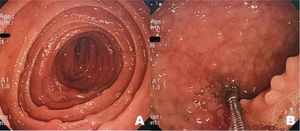

Upper gastrointestinal (GI) endoscopy revealed multiple elevated nodular lesions, smaller than 5 mm, at the level of the duodenum and the first jejunal segments. The lesions were rose-colored, as was the surrounding mucosa, and were present along the entire circumference of the organ (Fig. 1A and B).